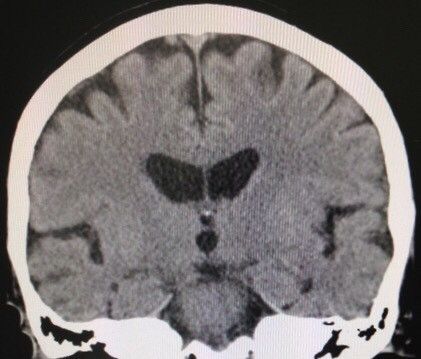

改訂長谷川式 11/30 遅延再生 0/6 頭部MRI(受診時)前頭葉と両側海馬の萎縮 錐体外路兆候及び行動異常 認めず。今年、3月初めに転倒。頭部CT上、血腫認めず。4月中旬、代診だったが、トイレに歩いて行けている、夜間に家の中を歩き回って困る等、歩行障害はなかった。5月中旬、「歩けなくなった」と受診。見当はついているので、脳外科を紹介。その返事に同封されていた写真が上のもの。無事にオペも終わり、元気であると、わざわざ、御家族が御礼の挨拶に来院され、近況を聞くことができた。でも、両側に血腫があるとは思っていませんでした。

80歳代 女性。昨年末から診療開始。改訂長谷川式 11/30 遅延再生 0/6 頭部MRI(受診時)前頭葉と両側海馬の萎縮 錐体外路兆候及び行動異常 認めず。今年、3月初めに転倒。頭部CT上、血腫認めず。4月中旬、代診だったが、トイレに歩いて行けている、夜間に家の中を歩き回って困る等、歩行障害はなかった。5月中旬、「歩けなくなった」と受診。見当はついているので、脳外科を紹介。その返事に同封されていた写真が上のもの。無事にオペも終わり、元気であると、わざわざ、御家族が御礼の挨拶に来院され、近況を聞くことができた。でも、両側に血腫があるとは思っていませんでした。